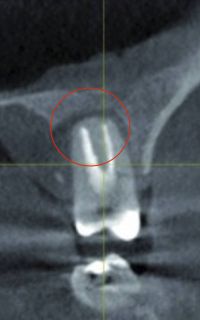

Bakterien toter, abgestorbener Zähne, welche eine Entzündung an der Wurzelspitze zeigen, produzieren Toxine, sog. Schwefelwasserstoffverbindungen, welche zu einer irreversiblen Hemmung am aktiven Zentrum vieler lebenswichtiger körpereigener Enzyme führen und somit vielfältige System- und Organ-Erkrankungen hervorrufen können.